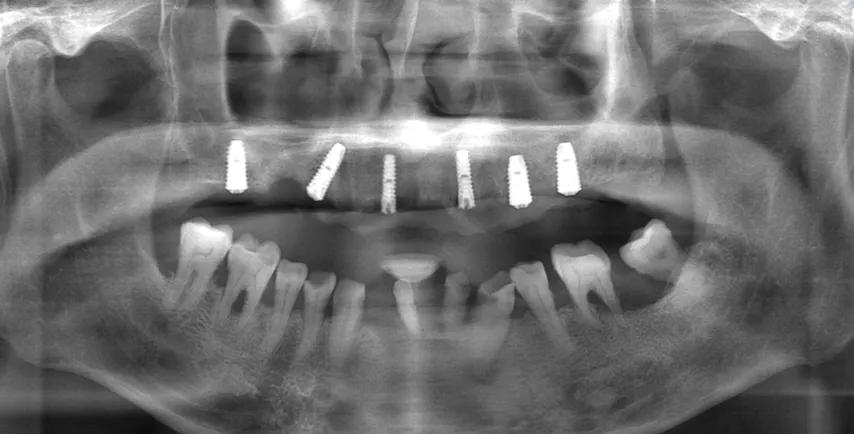

在南京做種植牙應(yīng)該找誰(shuí)?之前的時(shí)候?qū)ΨN植牙齒和口腔健康之類的問(wèn)題都模棱兩可也沒(méi)有過(guò)多接觸。也是我爸

的牙齒狀況越來(lái)越差,已經(jīng)到了影響正常生活的地步,平時(shí)吃飯都成問(wèn)題了,連芹菜這種硬度的食物都不太容易吃。家里才開(kāi)始對(duì)這方面的知識(shí)開(kāi)始留意,也開(kāi)始關(guān)注種植牙的問(wèn)題(因?yàn)榱私獾较鄬?duì)于假牙和補(bǔ)牙之類的種植牙確實(shí)是好的選擇,中間的過(guò)程就不過(guò)多贅述了),那段時(shí)間問(wèn)了很多朋友,也找了很多醫(yī)院,到后才確定在南京做種植手術(shù)的好的醫(yī)生是南京市口腔醫(yī)院的童昕主任。但是他的號(hào)確實(shí)在市口太難掛了,也是多方打聽(tīng)吧,后找的朋友(是童醫(yī)生的助手)才聯(lián)系上的。之后帶去童主任那里面診,制定的種植方案,因?yàn)楣橇咳笔в杏玫焦悄す欠郏钱吘辜依锢先俗龅氖前肟诘姆N植手術(shù),所以總體下來(lái)也算是個(gè)不小的費(fèi)用,可是能讓好好吃飯不再受罪才是好的,家有一老,如有一寶呀。